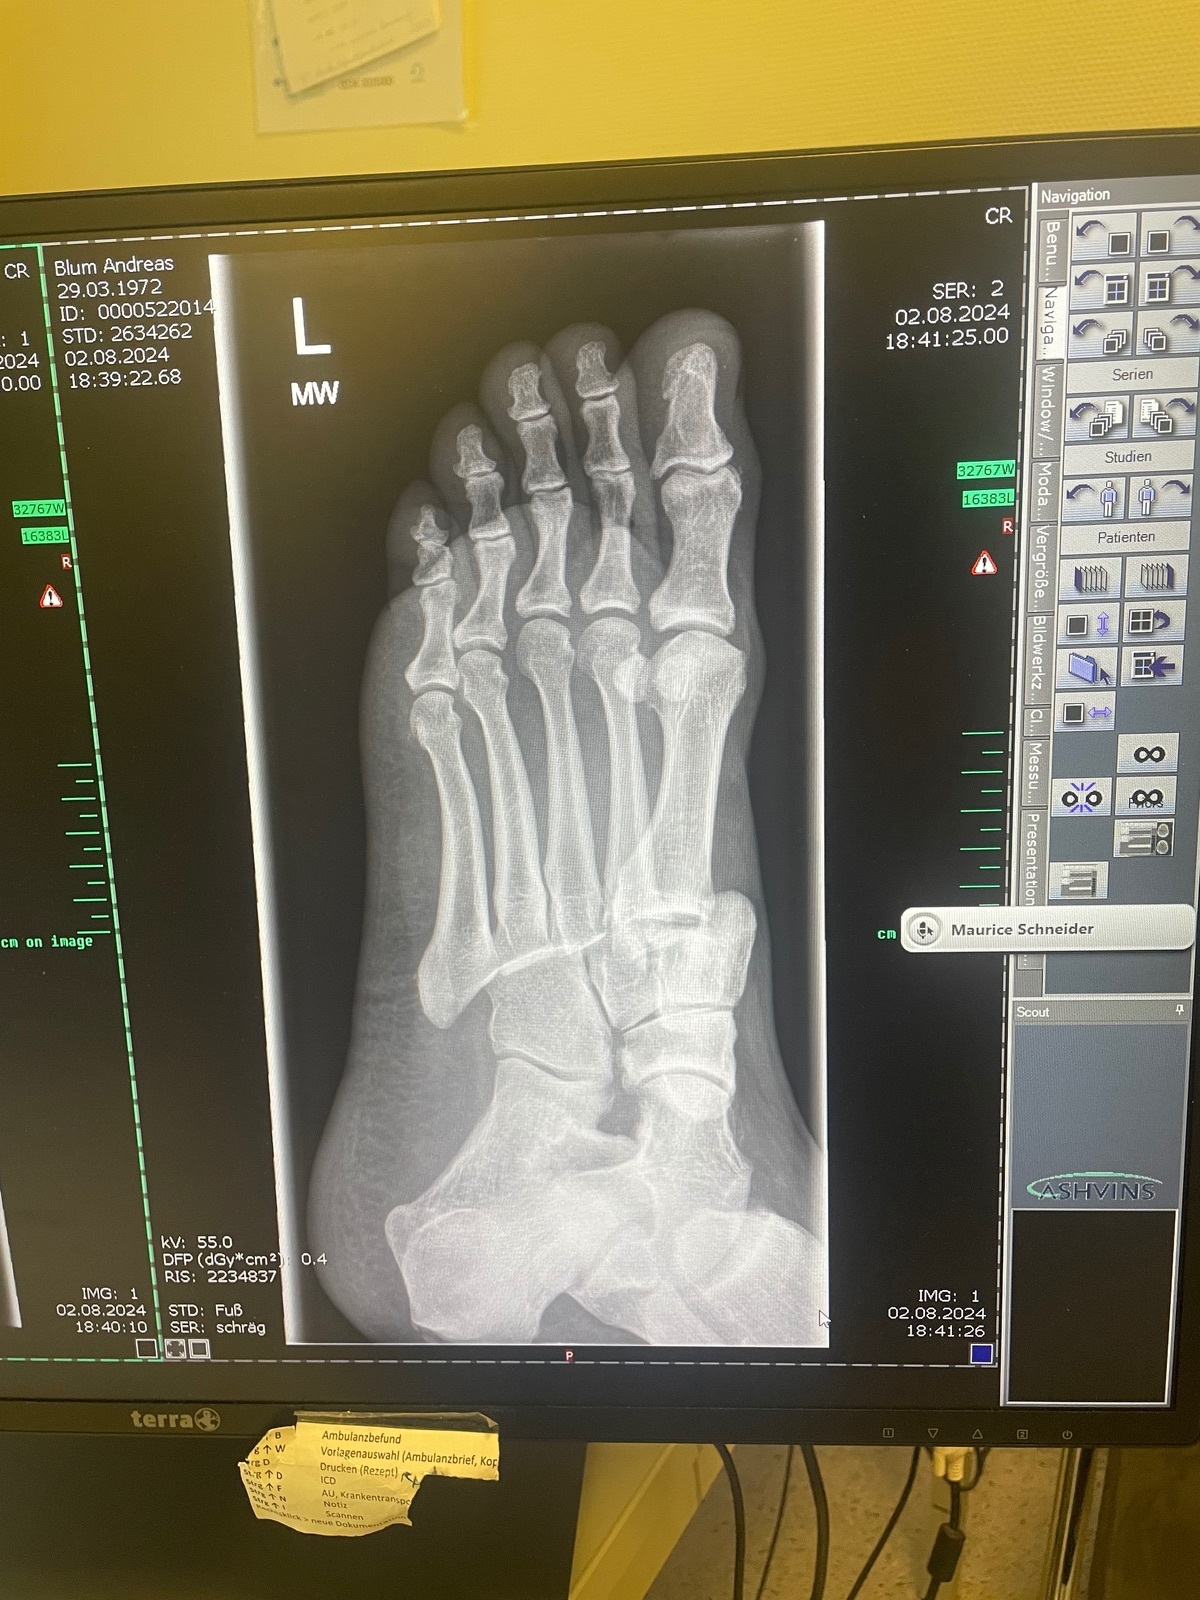

… und nach einer einstündigen OP und der ersten Nacht dieses:

Offensichtlich traf meine Fußraste oder ein anderes hervorstehendes Teil meinen Vorderfuß und klemmte den ein. Die Folge: alle Mittelfußknochen wurden aus der Position gedrückt und etwa „eine Zehe“ weiter nach links verschoben.

Die Sache nimmt mich für diese Saison aus dem Rennen und wird mich sicher 4-5 Monate beschäftigen, drei davon, ohne dass ich den Fuß belasten darf, anschließend Physio.